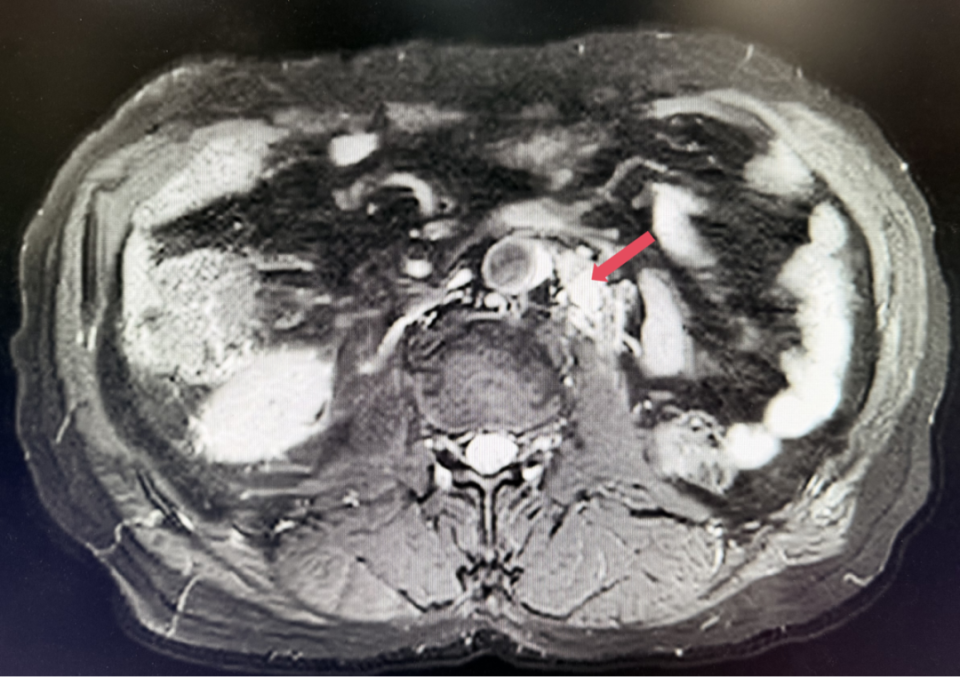

2025年1月:序贯为呋喹替尼单药(5mg,po,qd,D1-14,q3w)治疗。

2026年4月:持续维持PR,PFS超过37个月。

本例患者在一线培唑帕尼治疗进展后,参与到FRUSICA-2研究中,接受了呋喹替尼联合信迪利单抗二线治疗,在治疗6周后即达到了迅速缓解,取得超过37个月PFS,目前仍维持PR,帮助患者延长生存时间。回顾FRUSICA-2研究可见,呋喹替尼联合信迪利单抗的中位至缓解时间(TTR)为2.79个月,中位缓解持续时间(DoR)为23.69个月,进一步提示了该方案在缓解速度和长期维持缓解方面的表现。与此同时,患者治疗过程中不良反应轻微,耐受性佳,有助于患者回归正常生活。呋喹替尼联合信迪利单抗有望成为肾细胞癌二线治疗中的可考虑的一种治疗方案。